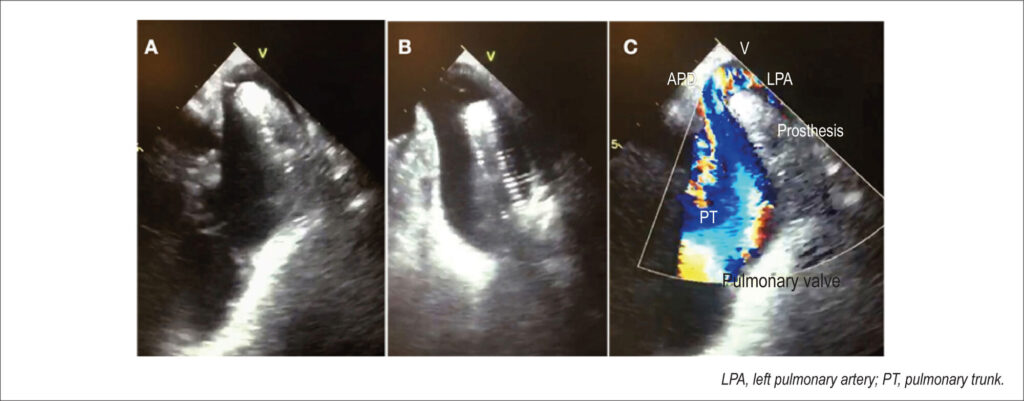

Figure 1

Transesophageal echocardiography images showing an Amplatzer™ prosthesis displaced to the pulmonary artery trunk (A and B). Color Doppler image showing turbulent flow in the pulmonary artery trunk (C).